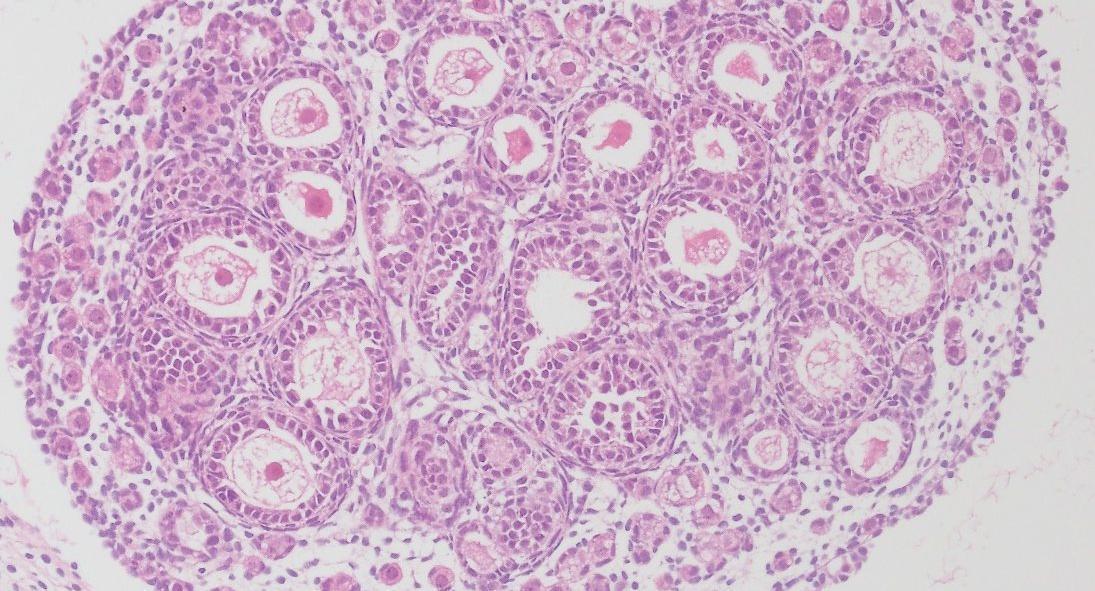

We investigate the genetic and epigenetic regulation of gonadal development and function, and its impact on gametes. To understand these processes, we integrate and apply omics approaches including chromatin proteomics, single cell sequencing and ATAC-sequencing, to cells derived from transgenic animal models as well as to samples donated by patients undergoing fertility treatments.

We focus particularly on understanding how the development of the ovarian follicles is controlled within the somatic cell lineages, in health and disease such as polycystic ovarian syndrome (PCOS), and the impact that this process has on long-term female fertility and oocyte quality.